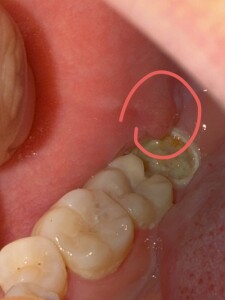

很大一溃疡,两周了还没好,之前没见过,今天一看很大一个,长在龋齿旁边,吃东西会痛

针对您描述的“龋齿旁边长了一个很大的溃疡,两周了还没好,吃东西会痛”的情况,这可能是由于多种因素导致的。以下是一些可能的原因、建议的治疗方法以及日常注意事项:

4. **牙齿问题**:龋齿严重时可能会导致口腔黏膜受损,从而出现口腔溃疡。此外,如果牙齿咬合关系不佳,也可能导致口腔黏膜受到摩擦和刺激,形成创伤性口腔溃疡。

3. **治疗龋齿**:如果溃疡是由龋齿引起的,应积极治疗龋齿。根据龋齿的严重程度,可以选择补牙、根管治疗等方法进行治疗。

如果症状持续加重或出现其他症状,建议及时就医进行专业诊断和治疗。